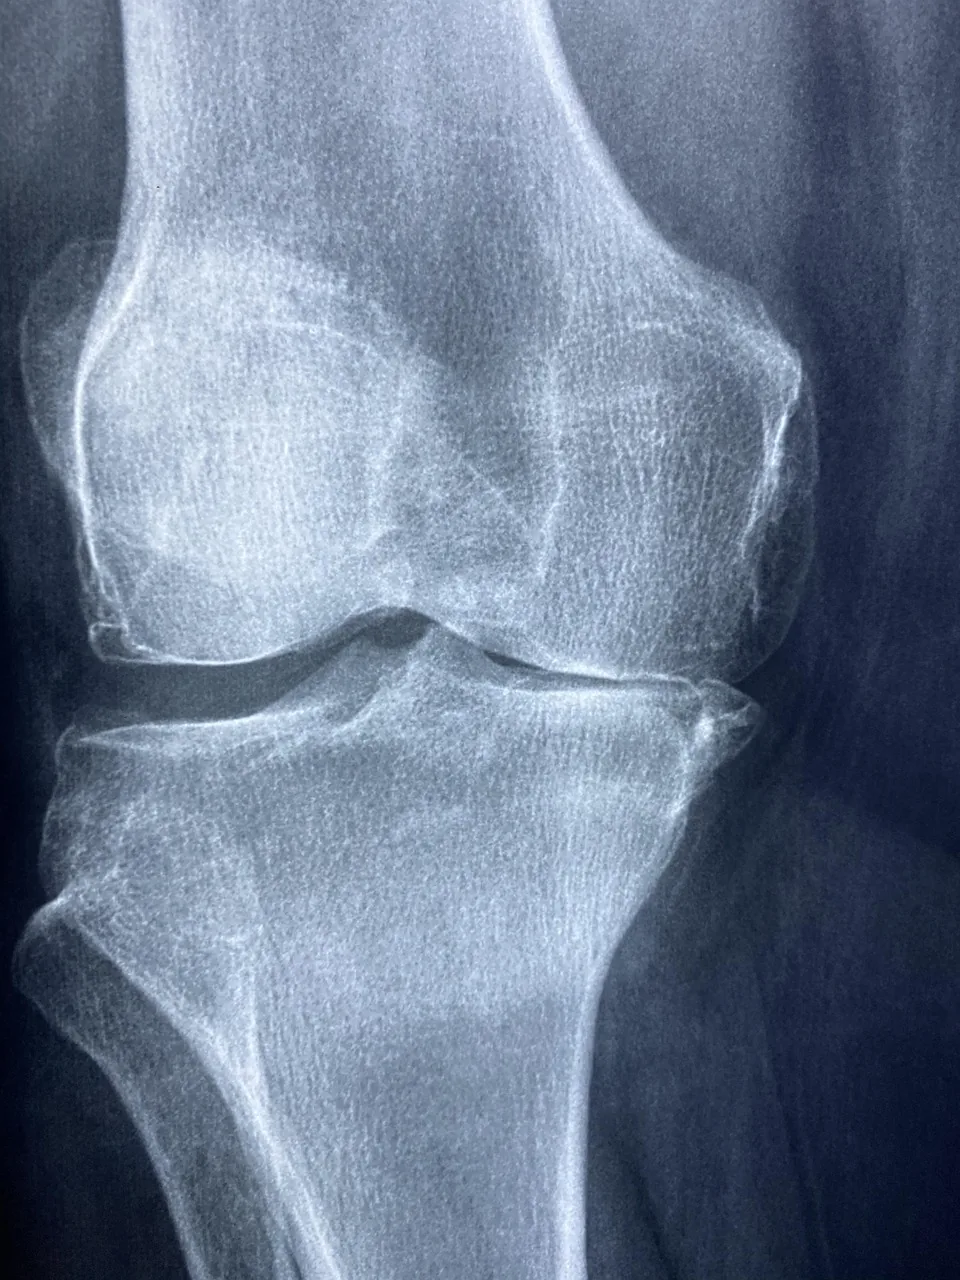

- 전문가 진료 및 검사

정형외과에서 병력 청취, 신체 진찰 후 X선, MRI, 관절경 등을 통해 조직 손상 유무를 확인합니다. - 약물 치료 및 주사 요법